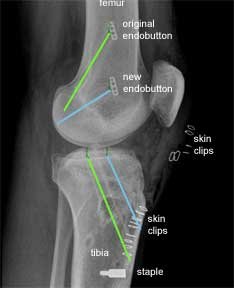

This is an X-ray, of the same patient, taken from the side instead of the front. The green lines show the original tunnels and the blue lines the new tunnels.

For the femoral tunnels the higher endobutton is from the original procedure and the lower endobutton is from the revision procedure.

The new tibial tunnel (blue) is more anterior (closer to the front) than the original tunnel. This is a more anatomic position for the tibial insertion of the native ACL.